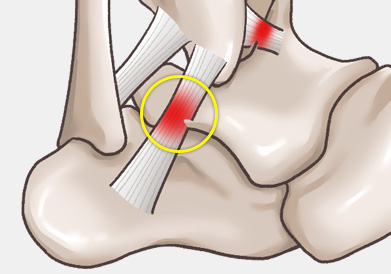

발목 인대 파열은 발목 관절을 지지하는 인대가 외부 충격이나 과도한 움직임으로 인해 늘어나거나 찢어지는 손상을 말합니다.

발목을 접질리거나 회전 손상을 입는 경우 발생할 수 있으며, 스포츠 활동 중, 낙상, 교통사고 등 다양한 원인으로 발생할 수 있습니다.

주로 다음 그림처럼 내반(inversion)에 의해 바깥쪽 인대가 파열되는 경우가 흔하며, 그 중에서도 전거비인대 및 종비인대의 손상 여부가 수술을 결정하는 데 가장 중요합니다.